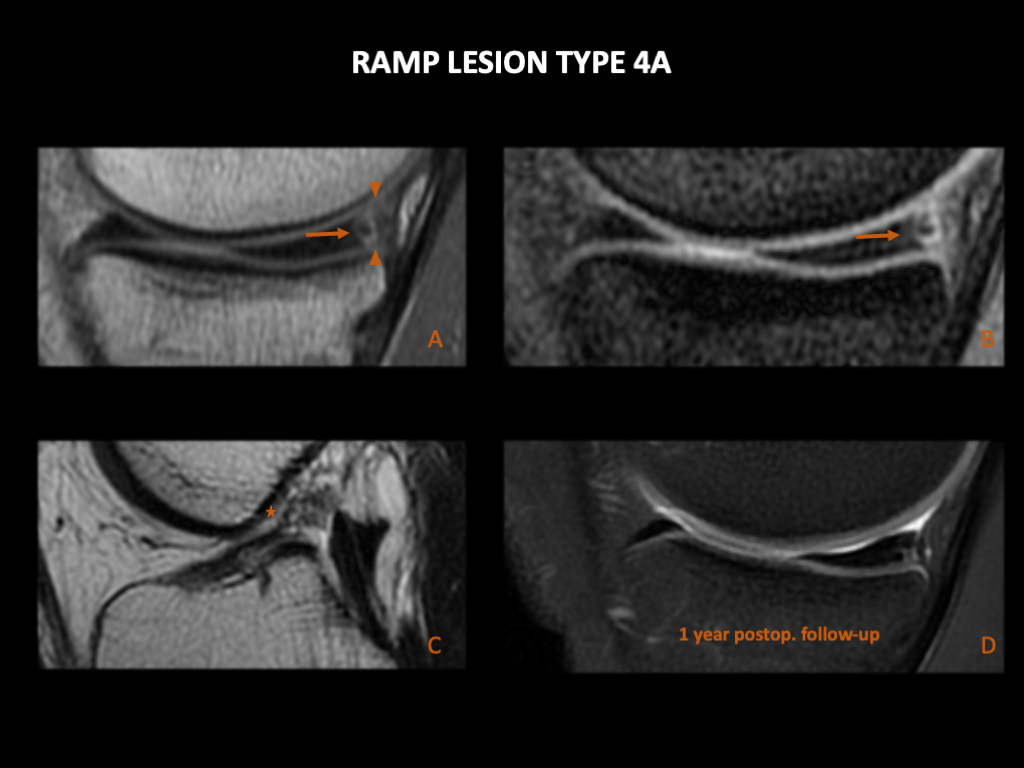

图 18:44岁,男性,左膝疼痛,出现Ramp损伤类型4A和半月板根部撕裂。左膝3T MRI (A) 矢状位PD FS,(B) 矢状位PD FS 和 (C) 冠状位T2WI FS。内侧半月板后角的“红区”有一条线性高T2信号(箭),达到上部和前部关节表面。这与Thaunat和Greif类型4A的半月板Ramp损伤一致。在图像B中,我们看到一个伴随的ACL撕裂(箭头)。在图像C中,可见内侧半月板后根部的高T2信号,与根部撕裂一致(双箭头)。(D):左膝关节镜,后内侧入路。内侧半月板的后根部已撕脱(星号)。

图 19:16岁,男性,左膝关节疼痛和不稳定,出现Ramp损伤类型4A。左膝1.5T MRI (A), (B) & (C):(A) 矢状位PD,(B) 矢状位GRE 和 (C) 矢状位T2。内侧半月板后角的“红区”有一条线性高T2信号(箭),达到上部和前部关节表面。半月板关节囊和半月板胫骨韧带完好(箭头)。这与Thaunat类型4和Greif类型4A的半月板Ramp损伤一致。在图像C中,观察到伴随的ACL撕裂(星号)。(D):术后1年的3T MRI,矢状位PD FS,(半月板缝合)。半月板呈波浪形,一些作者将其描述为半月板撕裂的间接征象,但在最初Ramp损伤发生的位置没有新撕裂的直接征象。